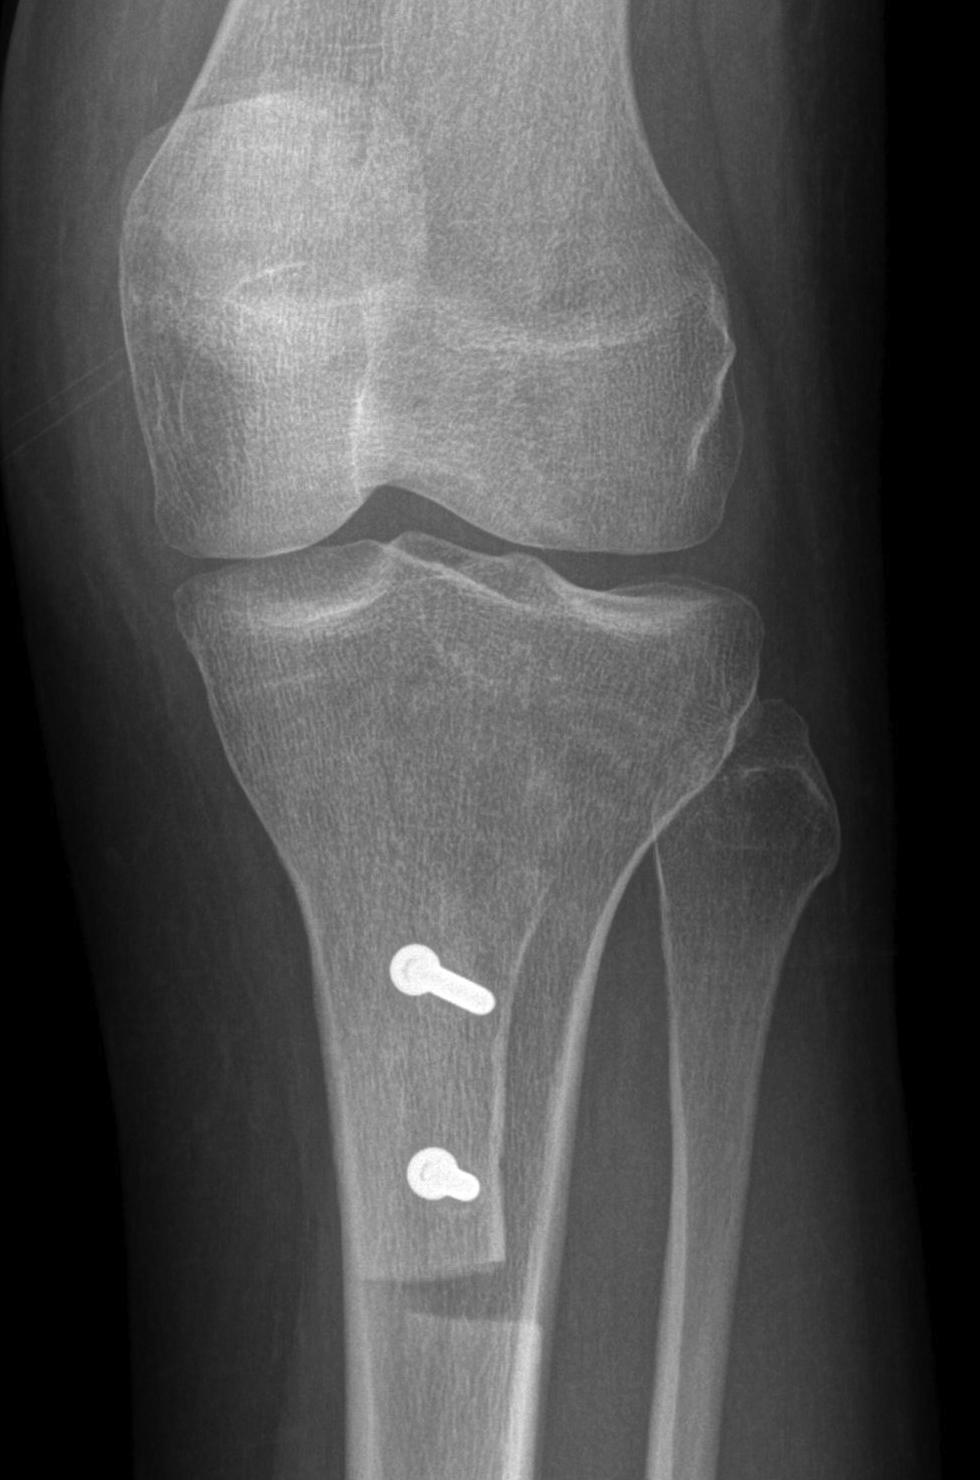

2. Perform TTT (if TTTG > 20)

- incision over TTT

- medialise at least 1 cm

- ensure some element of Fulkerson / anteriorise

- can distalise if patella alta

- secure with screws (2 x small fragment usually sufficient)

- reassess stability